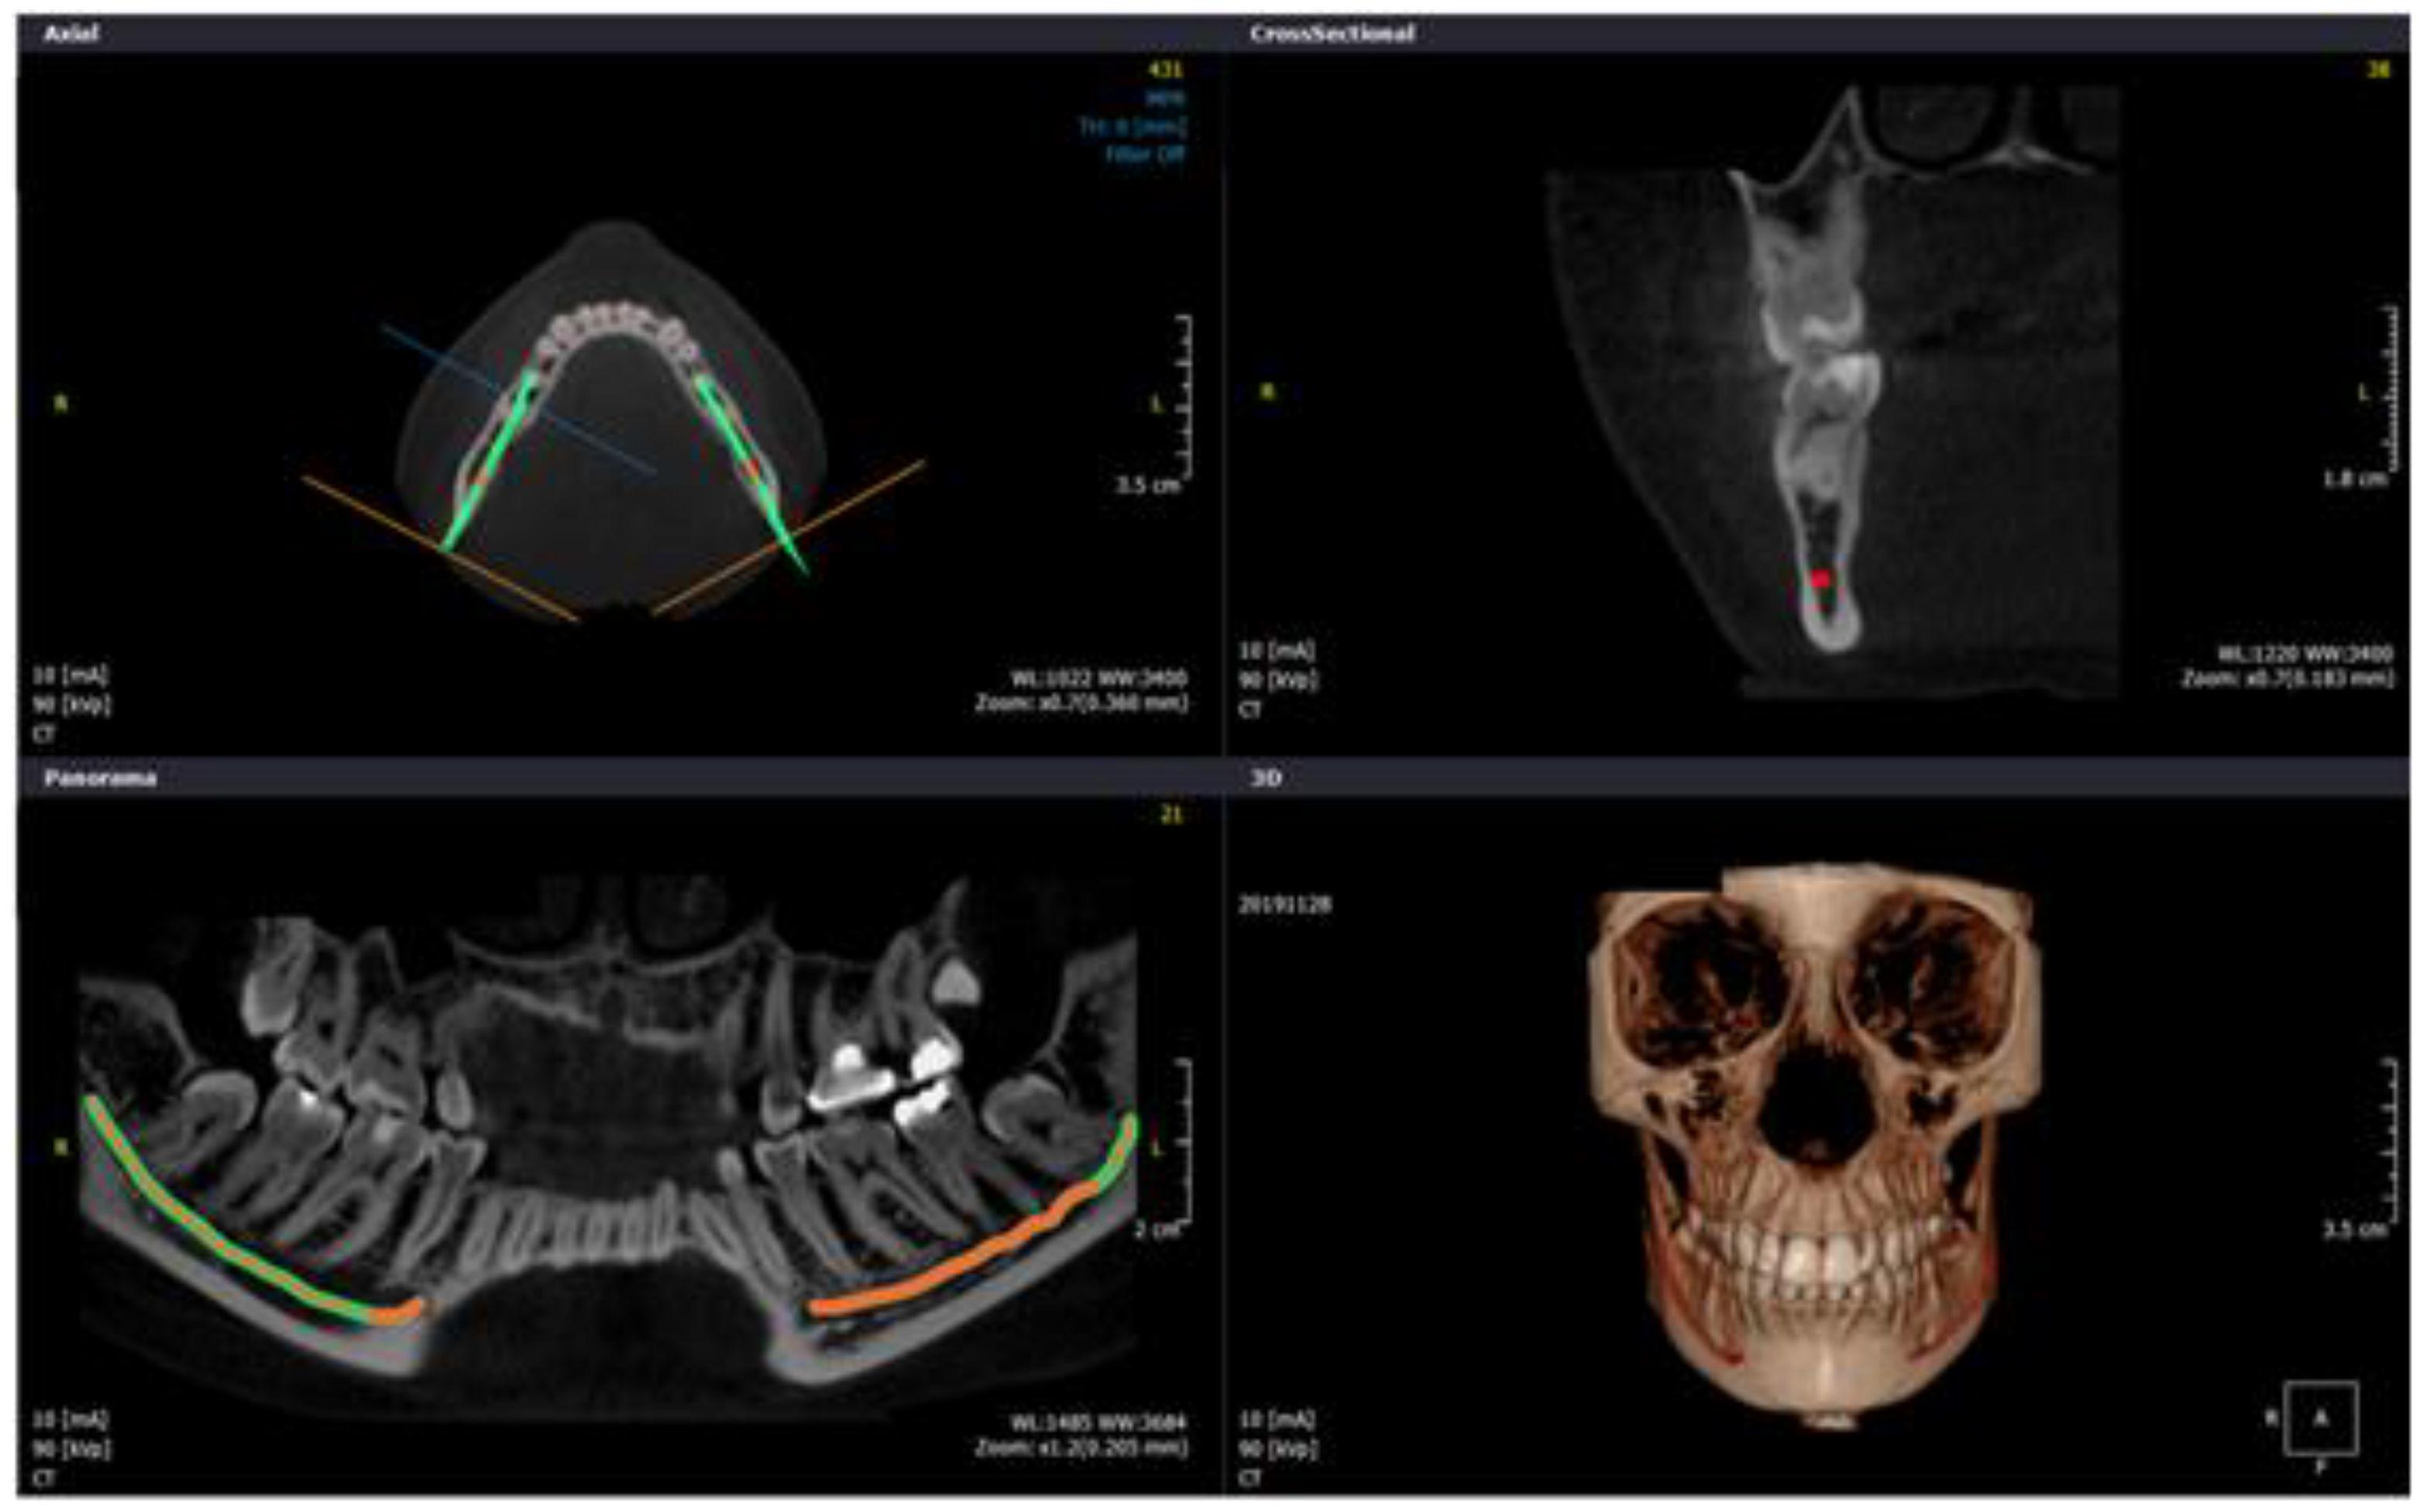

2.4. Study Protocol and Image Analysis

- Buccalcortical plate to IAN dimension (BCPN): Linear distance from the IAN to the nearest corresponding buccal outer cortical plate.

- Lingual cortical plate to IAN dimension (LCPN): Linear distance from the IAN to the nearest corresponding lingual outer cortical plate.

- Alveolar crest to IAN dimension (ACN): Linear distance from the IAN coronally to the midpoint of alveolar crest bone corresponding to the long axis of tooth.